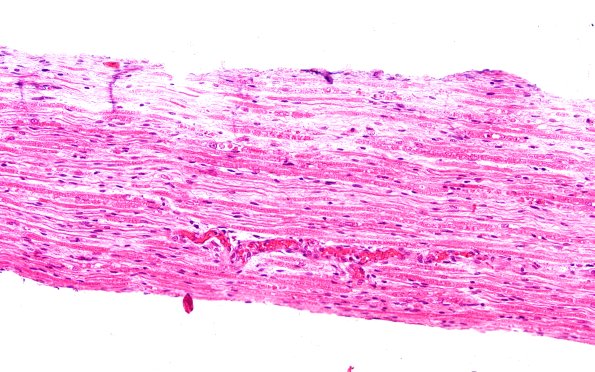

Washington University Experience | PERIPHERAL NEUROPATHY | 7A GUILLAIN-BARRE SYNDROME (GBS) | 5A1 (Case 5) H&E 20X 1

Case 5 No History ---- 5A1,2 Spinal roots show patchy pallor with minimal inflammation in longitudinal (5B1) or cross section (5B2). (H&E)